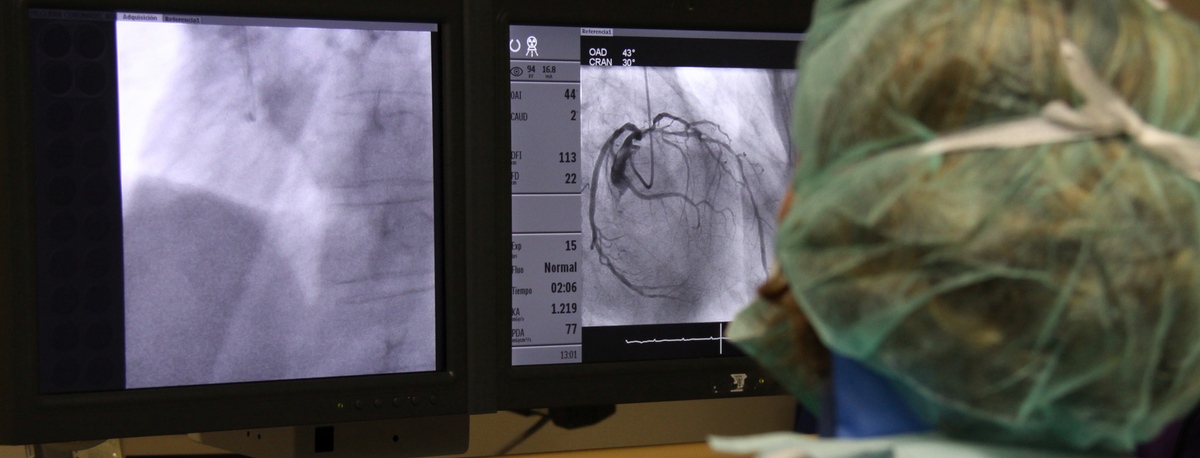

Instituto del Corazón

Instituto del Corazón Quirónsalud Teknon

Angiología, Cirugía vascular y endovascular

angiologia y cirugia vascularAngiología, Cirugía vascular y endovascular

Especialistas en cirugía arterial directa de extremidades, cirugía de varices, cirugía de aneurismas y cirugía carotídea

En el instituto contamos con especialistas en Angiología, Cirugía Vascular y Endovascular para el diagnóstico y seguimiento de las enfermedades del aparato circulatorio. La embolia cerebral y el tromboembolismo pulmonar son algunas de las principales causas de muerte debido a un problema vascular.

Nuestro equipo es especialista en técnicas mínimamente invasivas, utilizando técnicas endovasculares, sin cirugía, que permiten implantar prótesis vasculares para resolver dilataciones o aneurismas de las arterias. También ofrecemos todos los tratamientos de la patología venosa y arterial periférica, incluyendo las enfermedades de las arterias carótidas.